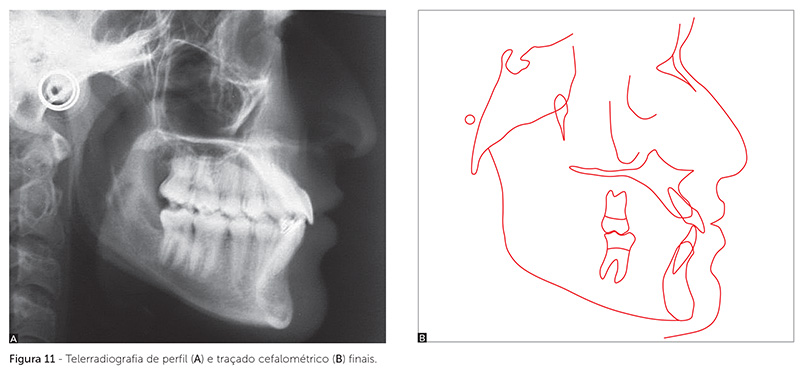

O traçado cefalométrico e a telerradiografia finais (Fig. 11, Tab. 1) evidenciaram que os incisivos superiores terminaram o tratamento com projeção elevada (1-NA = 36° e 1-NA = 10mm) porém adequados clinicamente, enquanto os incisivos inferiores terminaram bem posicionados (1-NB = 25°, 1-NB = 6mm e IMPA = 92°). Ao final do tratamento, a mandíbula mostrou posicionamento mais anterior em relação à maxila, comparativamente à fase inicial, com o ANB = -1° e ângulo da convexidade = -0,5°, medidas dentro de um padrão clinicamente aceitável. O plano mandibular mostrou suave movimento anti-horário, verificado pela diminuição dos ângulos relacionados ao plano mandibular (SN-GoGn e FMA) e do Eixo Y.

Analisando-se as sobreposições dos traçados cefalométricos, verifica-se que, durante o tratamento, houve maior crescimento mandibular em relação à maxila no sentido horizontal (Fig. 12). Uma possível explicação para a movimentação anterior reduzida do ponto A, em relação ao ponto B, durante o tratamento, evidenciando menor crescimento da maxila em relação à mandíbula, pode ter sido a grande vestibularização ocorrida nos incisivos superiores. O aumento da inclinação dos incisivos superiores, com consequente movimento palatino de raiz, pode ter influenciado de maneira a posicionar o ponto A mais posteriormente, dando a falsa impressão de um crescimento deficiente de maxila.